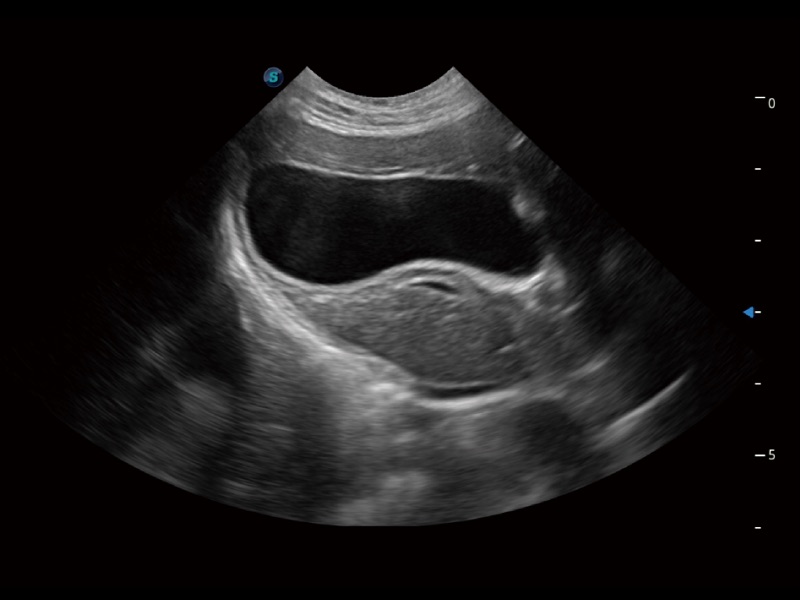

猫、中小型犬及小型异宠动物

ProPet 70 进一步提升了微米成像算法,更加注重对基础原始图像的还原和保留,在有效减少斑点噪声、增强组织边界显示的同时,避免过度优化丟失真实的解剖信息。

ProPet 70专为动物医生设计,对不同的动物体型和生理结构作出了针对性的优化。通过动物影像专用软件,可满足个性化的应用需求,帮助动物医生获得更精确的诊断数据。